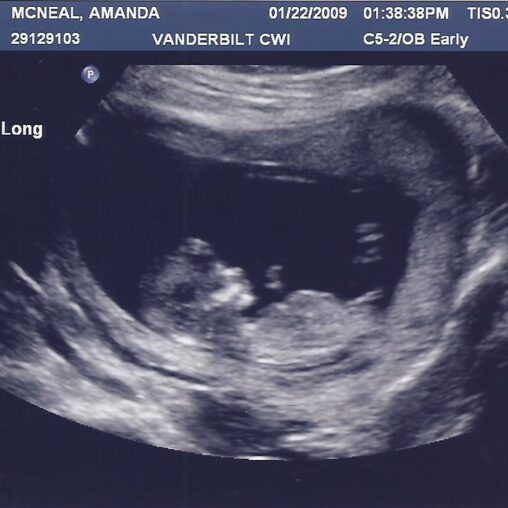

The pro-choice side has long been considered the side of science, but, as technology has evolved, so has the evidence for the pro-life argument. As Jeanne Mancini, the president of March for Life, said: “There had been, a long time ago, this mantra from our friends on the other side of this issue that, while a little one is developing in its mother’s womb, it’s not a baby. It’s really hard to make that argument when you see and hear a heartbeat and watch little hands moving around.” It is no longer reasonable for pro-choice arguments to say that the fetus is not a baby. As any ultrasound will show, that is just plain wrong.

Picture: “Ultrasound A 12 weeks 3 days 001” by Amanda’s Adventures is licensed under CC BY-NC-ND 2.0